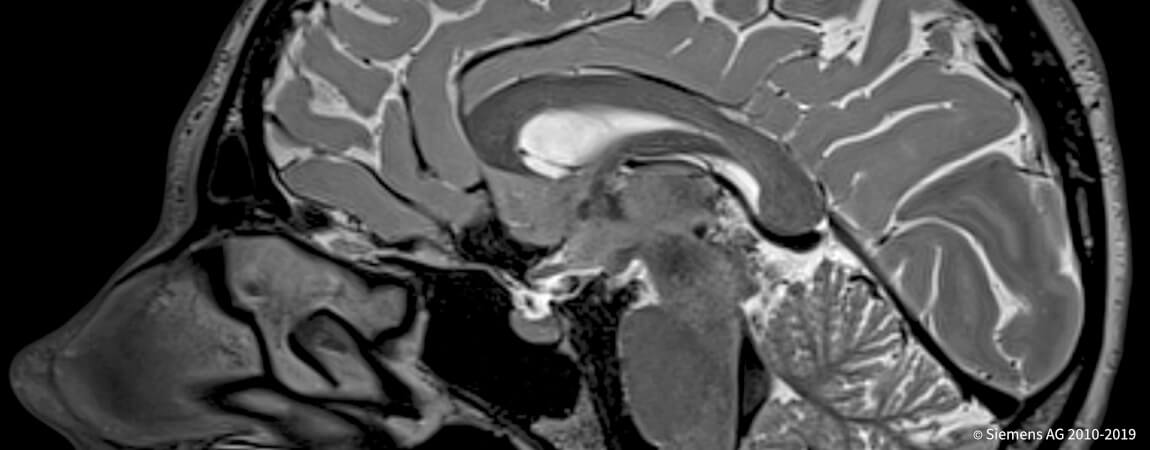

- _Все методы томографии